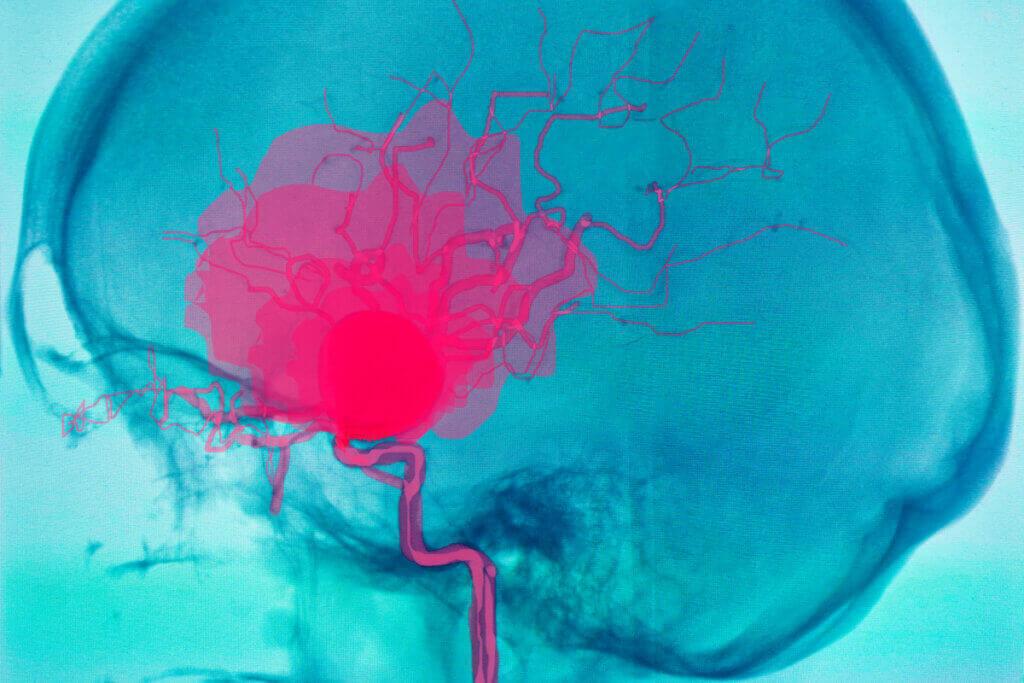

No humano, o sistema circulatório é constituído pelo sangue, por um conjunto de condutos (veias, artérias e capilares, entre outros) e pela bomba motriz conhecida por todos: o coração. É necessário distinguir cada estrutura em um nível fisiológico, uma vez que várias patologias circulatórias variam em gravidade e prognóstico dependendo do local afetado.